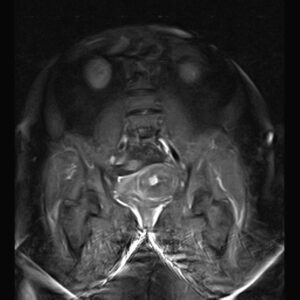

PELVIC MRI

( with & without contrast)

REPORT:

The urinary bladder appears normal and has normal wall thickness.

– Multiple intra mural – subserosal myoma :

1. ( 40 x 45 mm ) in right side of fondus

2. ( 20 x 22 mm ) & ( 20 x 25 mm ) in right side of body

3. ( 48 x 55 mm ) in left side of body

– Both ovaries are atrophied & without follicles .